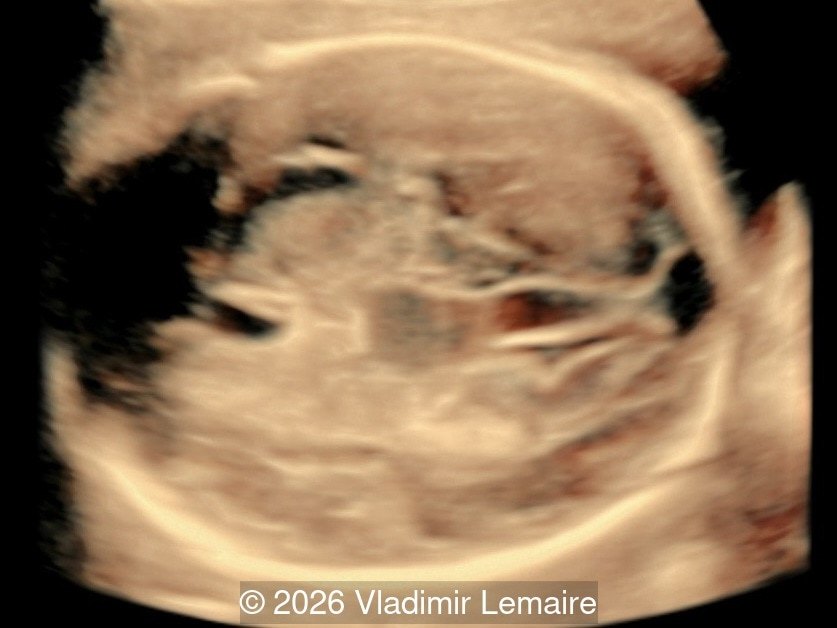

Sagittal 3D glass-body mode demonstrates the arteriovenous fistula between the deep choroidal arteries and the embryonic median prosencephalic vein of Markowski.

Image 3 Sagittal 3D glass-body mode demonstrates the arteriovenous fistula between the deep choroidal arteries and the embryonic median prosencephalic vein of Markowski.

Our imaging revealed enlargement of the fetal heart with dilation of the superior vena cava. On further evaluation, we identified an elongated anechoic cystic structure in the midline of the head, without mass effect on the surrounding structures. Color doppler demonstrated an arteriovenous fistula between the deep choroidal arteries and the embryonic median prosencephalic vein of Markowski. The vein of Galen aneurysmal malformation was likely the contributing factor to the cardiac enlargement. Cardiac function was, however, preserved and hydrops not present. Additional images are shown below.

A vein of Galen aneurysmal malformation (VGAM) is a space-occupying lesion that results from an arteriovenous fistula between deep choroidal arteries and the median prosencephalic vein of Markowski. The vein of Markowski drains into the vein of Galen, thus the lesion is not a true aneurysm, but the term is still commonly used to describe this fistula. A VGAM is rare and accounts for less than 1% of all vascular malformations. It is, however, the most common type of arteriovenous malformation in the fetus. A VGAM is present in the first trimester, between weeks 6 to 11, but its effects such as dilation, cerebral compression, and cardiac volume overload may not be seen until the second and third trimester.

On ultrasound, a VGAM appears as an elongated anechoic cystic structure in the middle of the head, often without mass effect on the surrounding structures. Color Doppler shows high-velocity flow in the lesion and can be used to identify the arteries feeding the vascular malformation. Pulsed-wave Doppler shows markedly turbulent flow. Additional key echocardiographic features include an enlarged heart with preserved systolic function, a dilated superior vena cava, and mild or moderate tricuspid regurgitation. Tricuspid regurgitation was not present in our case at the time of our evaluation.